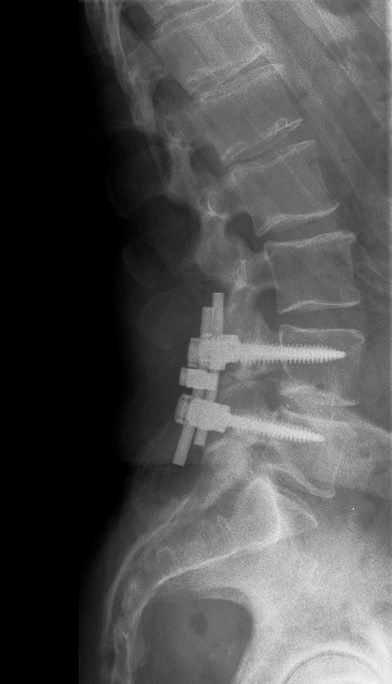

Spondylodese

Bij ernstige artrose en of stenose worden wervels soms operatief vastgezet. Dit noemt men spondylodese. Zie afbeelding hieronder.

De wervels die zijn vastgezet kunnen niet meer bewegen, hierdoor worden andere wervels meer belast. De fysiotherapeuten van fysiotherapie Arnhem kunnen u helpen om de wervels die niet vastgezet zijn te mobiliseren, zodat uw rug soepeler wordt.